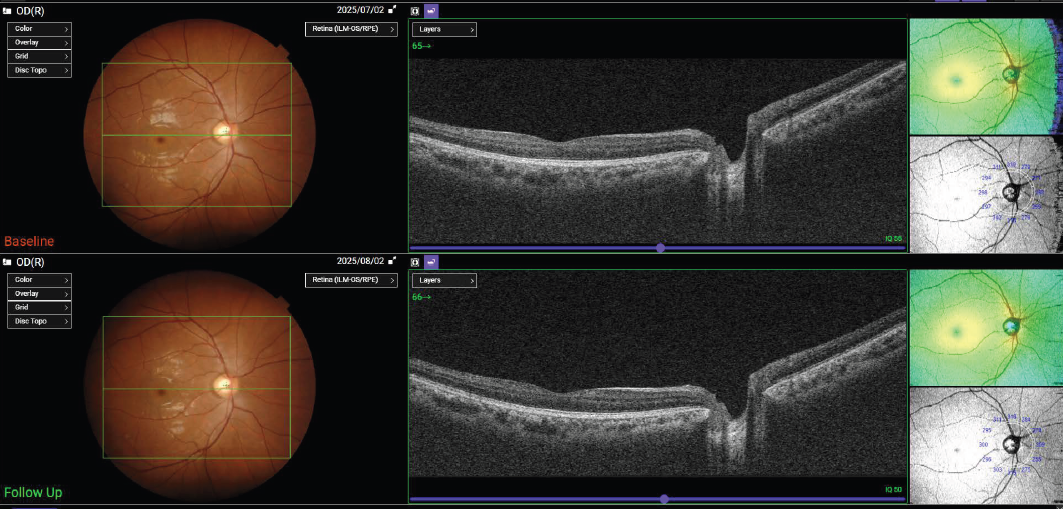

FUNKCIJA PONOVNEGA ZAJEMA(Follow-Up Function)

Funkcija ponovnega zajema omogoča enostavno ponovno pridobivanje in ponovno analizo iste lokacije, kar omogoča nemoteno primerjavo preteklih in trenutnih podatkov. Operaterji preprosto izberejo prejšnje podatke skeniranja, Triton2 pa samodejno zajame ustrezno območje.